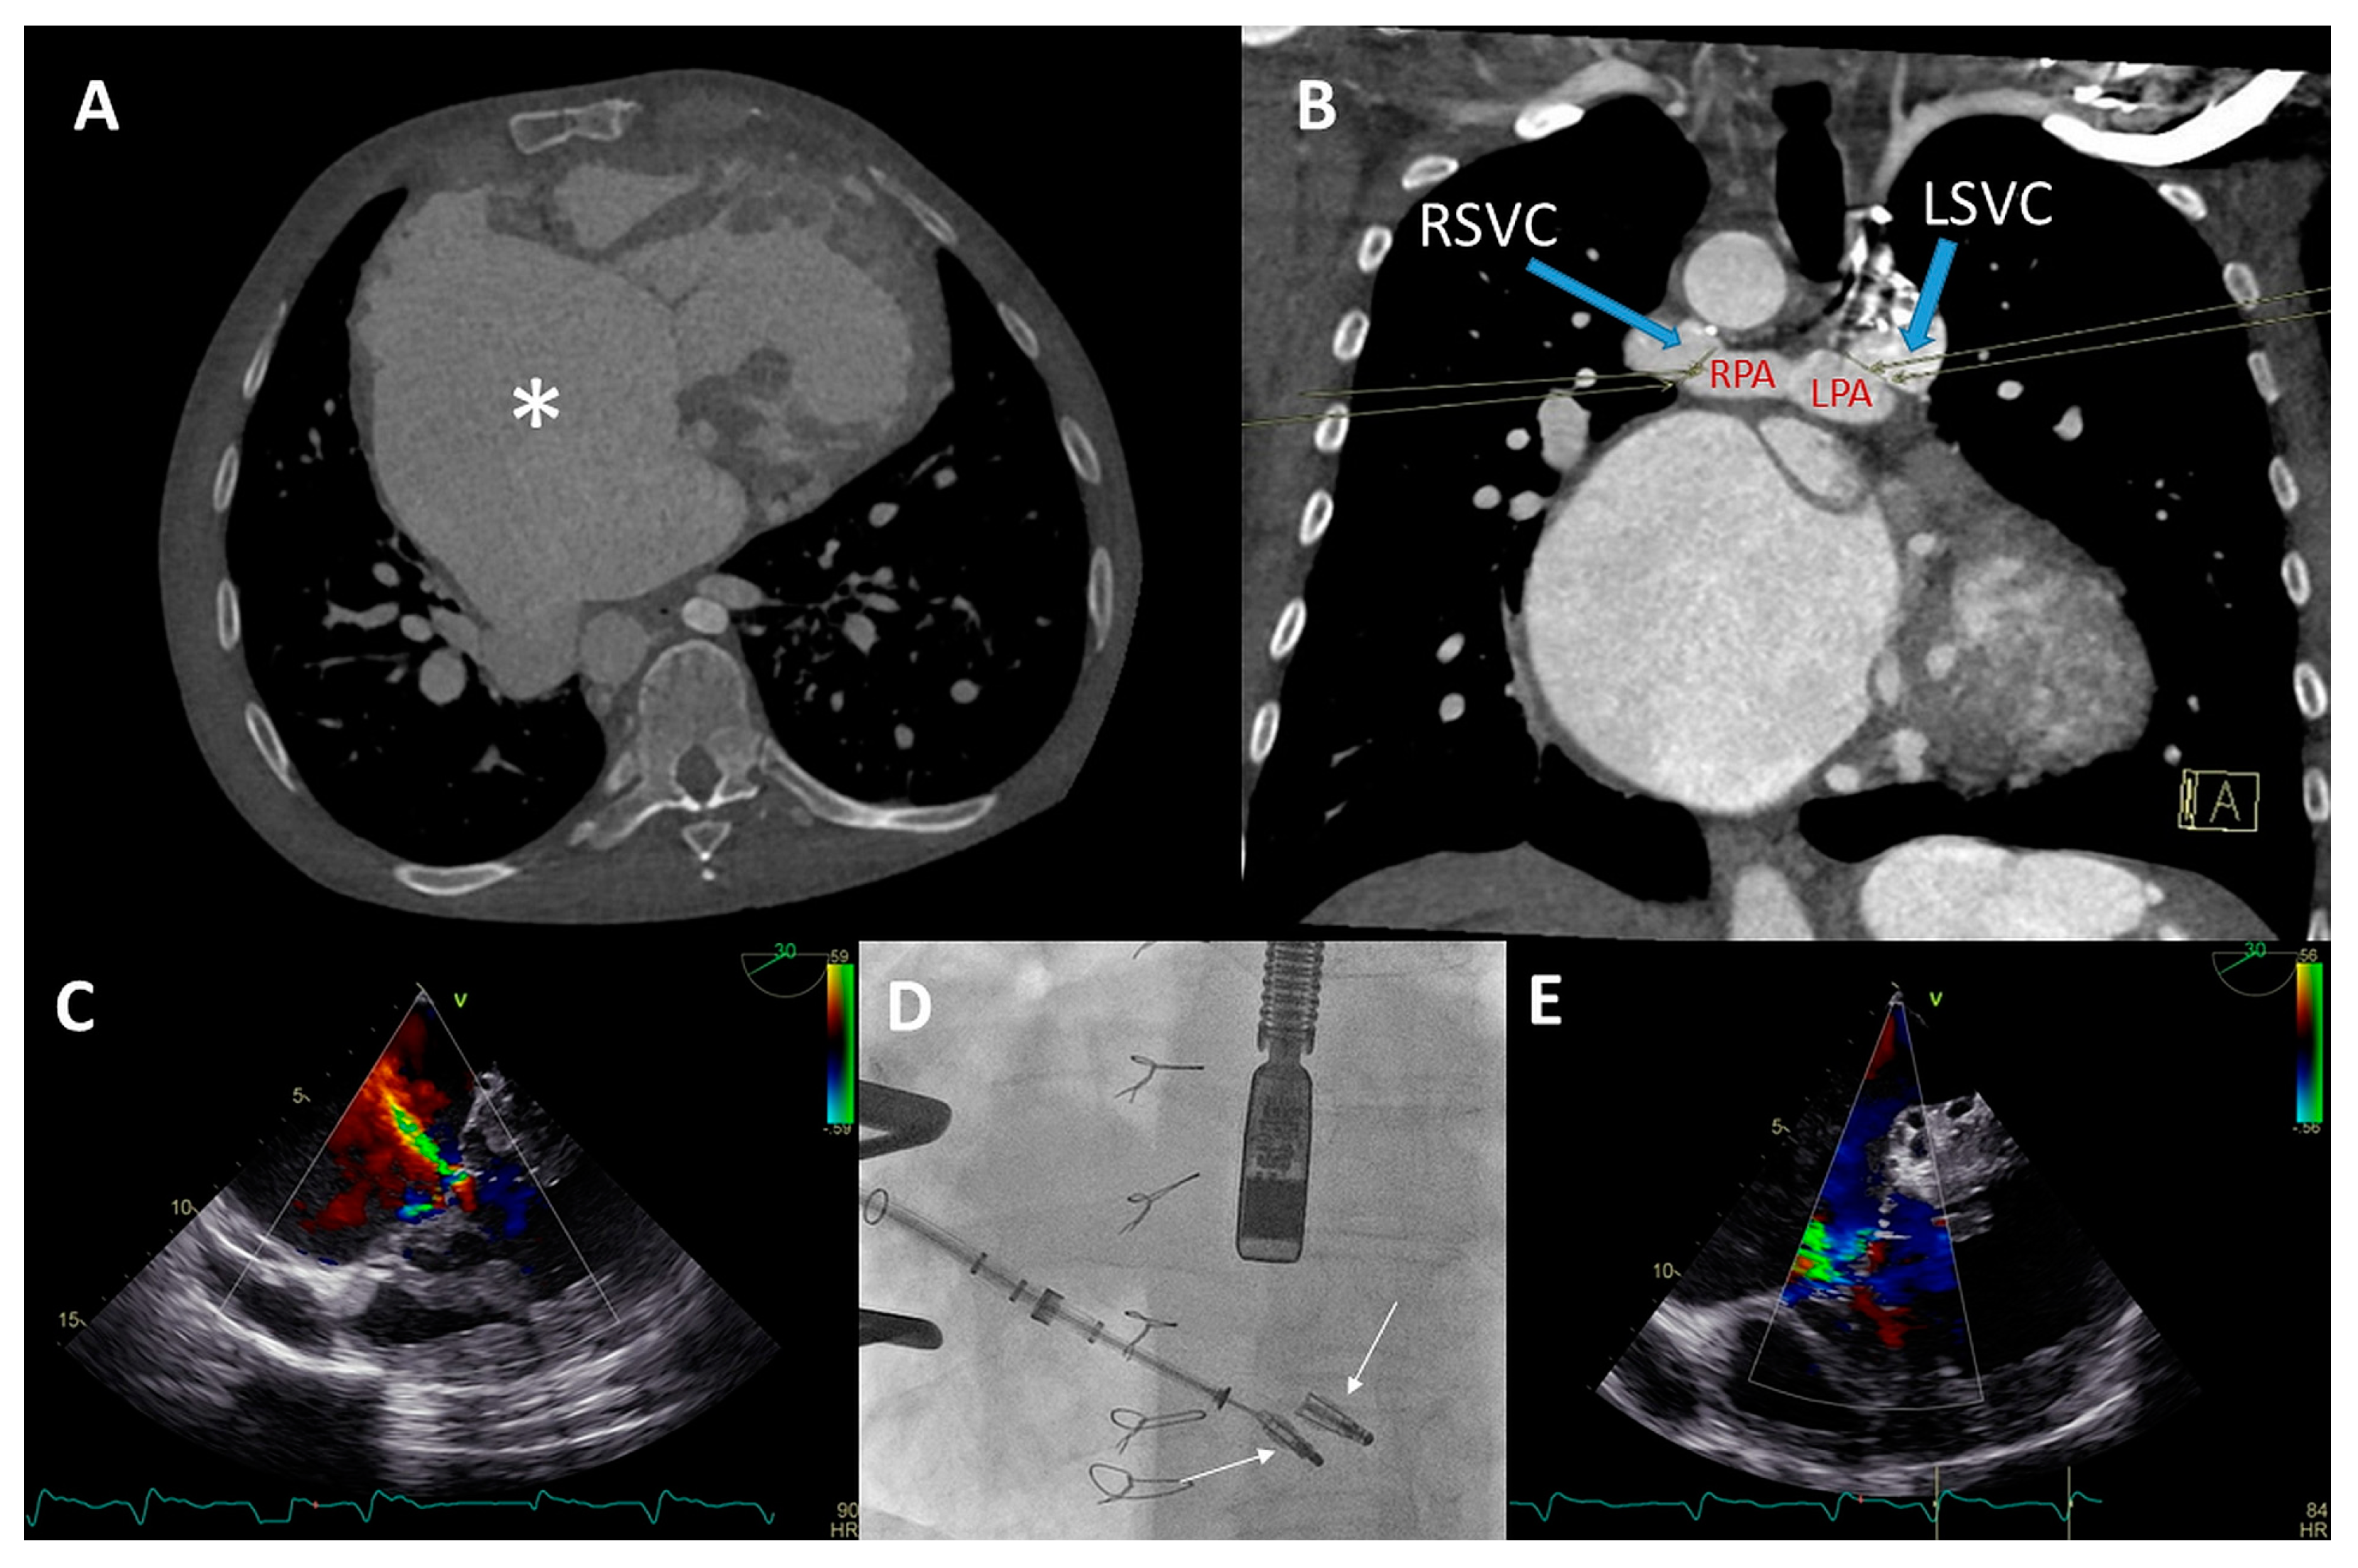

(A) Color Doppler apical four-chamber view shows severe tricuspid regurgitation (TR) with a wide vena contracta (arrow) and a systolic jet reaching the roof of the enlarged right atrium (RA). (B) Color Doppler showing turbulent inflow through the tricuspid valve (TV) bioprosthesis and aliasing, mean gradient was elevated at 4–5 mmHg. (C) Continuous wave Doppler showing a dense TR signal with low velocity. (D) Calcified and degenerated tricuspid bioprosthesis (arrow). (E) Axial slice through a computed tomography (CT) scan at the level of the right ventricle shows a giant RA and an intra-atrial septum deviation towards the left atrium (arrow), partially suppressing it. (F) Sagittal CT slice shows the inflow angle of the inferior vena cava-right RA and the RA-TV. Note the distended hepatic vein (HV). (G,H) Right anterior oblique fluoroscopy projections show the expansion of the Sapien 3 valve (asterisk) using the ring of the degenerated bioprosthesis as the reference and the final result, respectively. (I,J) Apical four-chamber color Doppler views showing normal function of the valve-in-valve bioprosthesis (appreciate the difference with (A,B), respectively). (K,L) View of the valve-in-valve bioprosthesis in systole (closed) and diastole (open), respectively.

This was successfully performed under local anesthesia, by means of right femoral access and fluoroscopy and TTE guidance. A temporary pacemaker wire was placed in the left ventricle and the AgilisTM steerable introducer (Abbott, IL, USA) was used to safely access the RA, given the relatively sharp angle between the vena cava-RA and the RA-RV axis (Figure 4F). The Edwards eSheath TM (Edwards Lifesciences, USA) was then used to implant a 29 mm Edwards SAPIEN 3 valve (Edwards Lifesciences) in the TVR bioprosthesis under rapid pacing (Figure 4G,H). Normal function of the new valve-in-valve bioprosthesis was confirmed by transthoracic echocardiography (Figure 4I–L). The periprocedural course was uneventful. At 22 months follow-up, the patient is in NYHA functional class I with moderately reduced (yet significantly improved) RV function and normal function of the bioprosthesis.